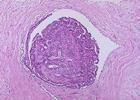

乳管內乳頭狀瘤多見於經產婦,40—50歲為多。75%病例發生在大乳管近乳頭的壺腹部,瘤體很小,帶蒂而有絨毛,且有很多壁薄的血管,故易出血。發生於中小乳臂的乳頭狀瘤常位於乳房周圍區域。

乳管內乳頭狀瘤屬良性,但6~8%的病例可發生惡變。